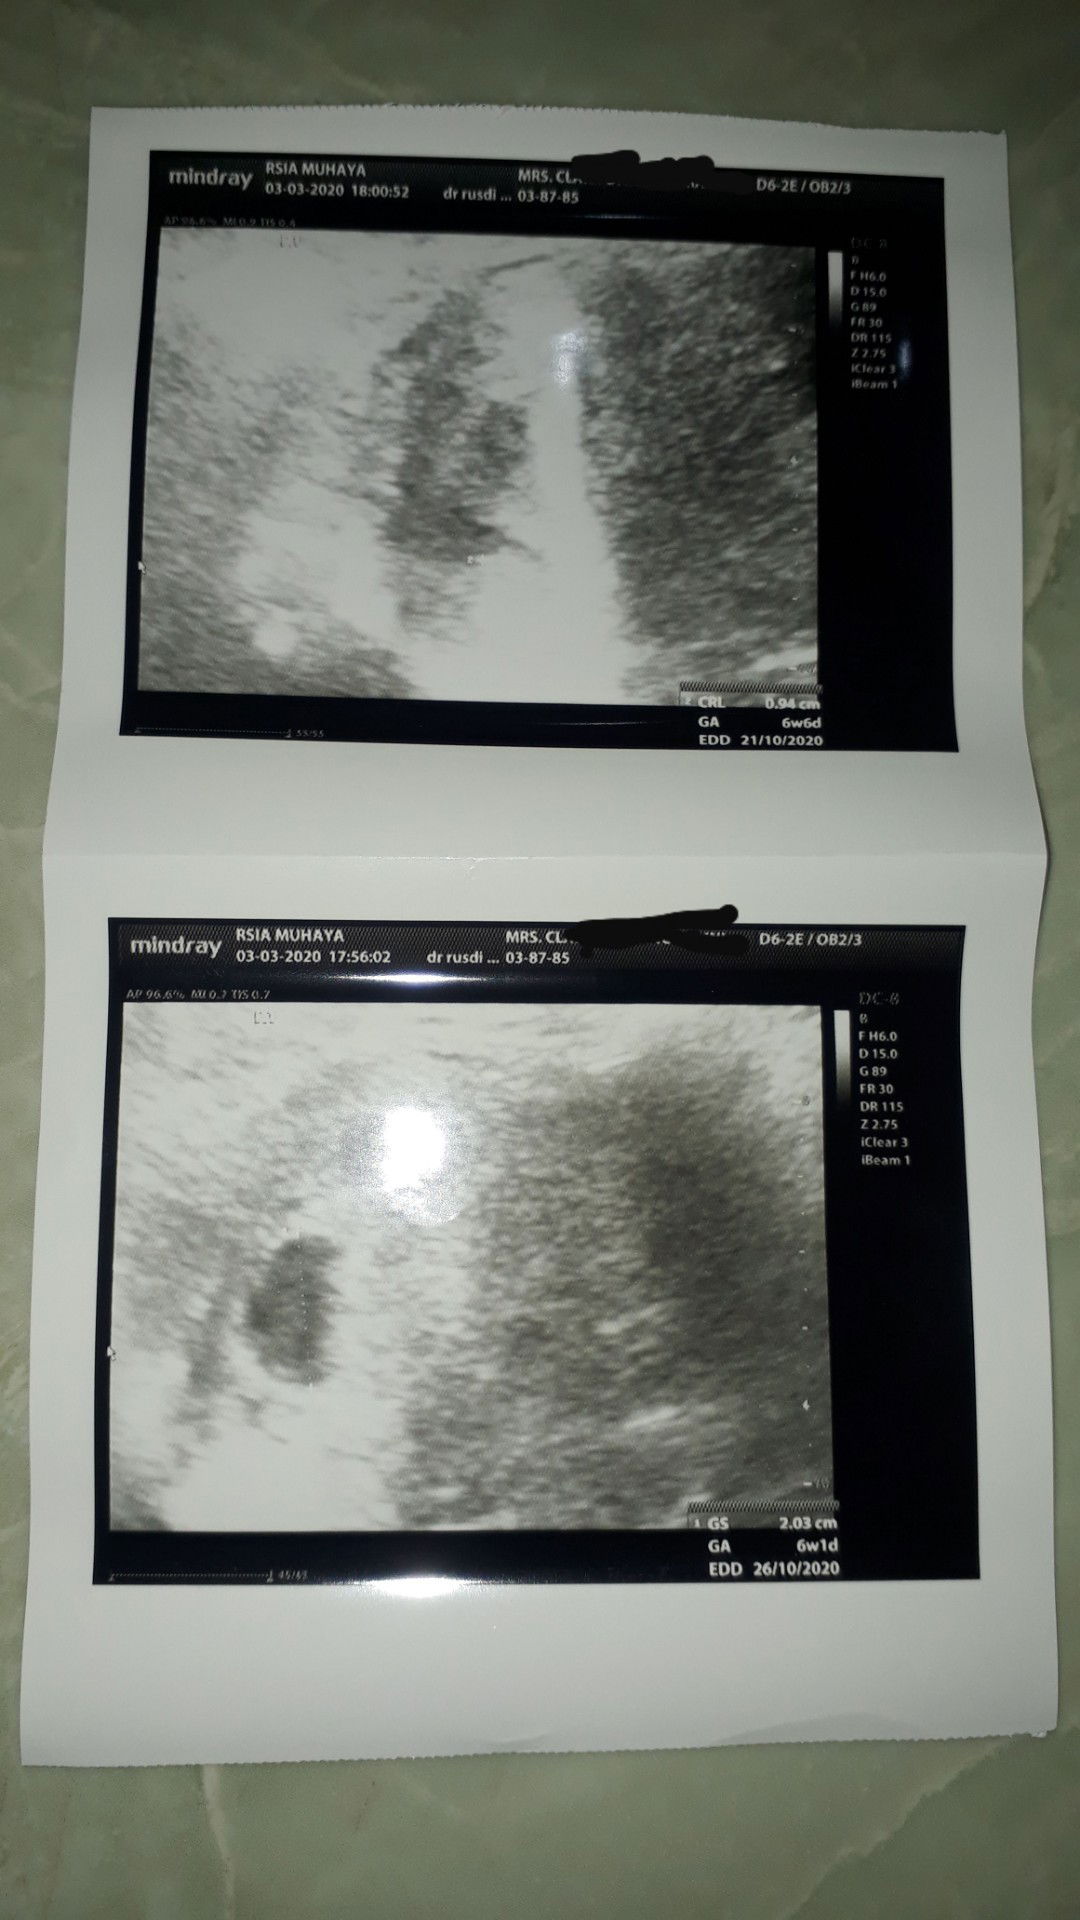

hamil kembar

Assalamualaikum. Mau tanya dong bun ,ada nggak disini pas cek TM 1 khmilan 1 kantong nya udah ad janin dan 1nya lagi msib kosong . Sya usg 6w2d 1 kntong bawah udah ad janin yg atasnya masih kosong . Doain y bun 2.2 ny brkmbg dan sehat . Aamiin

usg 6week

Alhamdulillah td usg krn mlm kmrn aku flek lagi, jd dpaksain suami td usg , dan alhamdulillah pas usg trnyta kembar , 1kantong bawah dedekny udh kliatan denyut jantungnya ud kdgrn , bahagia skli . Tp yg kantong atas masih trlihat kantong dn msih mnunggu prkmbgnnya . Doakn ya bunda2 biar kita smua yg sdg hamil sehat bayi dan ibunya smpe lahiran , dan yg blum hamil smoga dsegerakan hamil . Aamiin aamiin aamiin❤